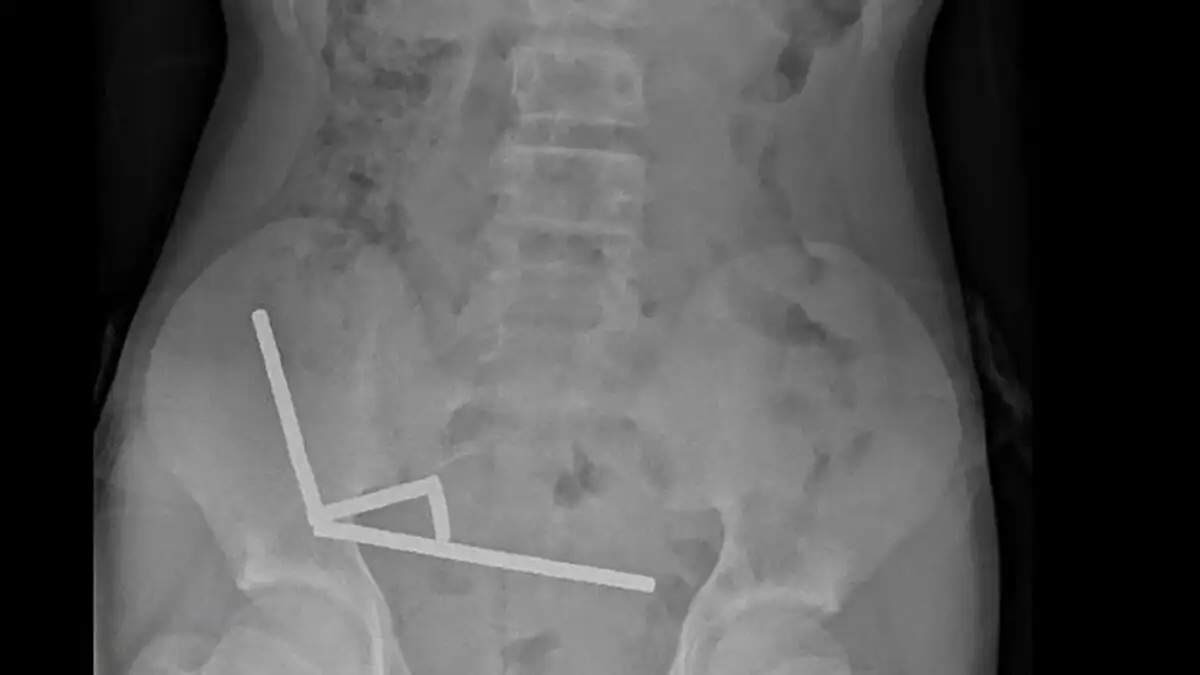

Μια σοκαριστική περίπτωση αντιμετώπισαν οι γιατροί στη Νέα Ζηλανδία, όταν ένας 13χρονος κατέληξε στο χειρουργείο αφού είχε καταπιεί δεκάδες ισχυρούς μαγνήτες, προκαλώντας σοβαρές βλάβες στο έντερό του. Κατάπιε περίπου 100 μαγνήτες και υπέφερε για μέρες Το περιστατικό καταγράφηκε στο νοσοκομείο Ταουράνγκα, στο βόρειο τμήμα της Νέας Ζηλανδίας, όπου το ανήλικο αγόρι διακομίστηκε ύστερα από τέσσερις […]Μετάβαση στην Πηγή ALLDAYNEWS